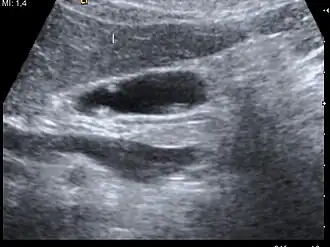

| A polyp in the gall bladder as seen on ultrasound |

Diagnosis is typically by ultrasound or CT imaging.

Ultrasound image of gallbladder polyps measuring 3–7 mm. -